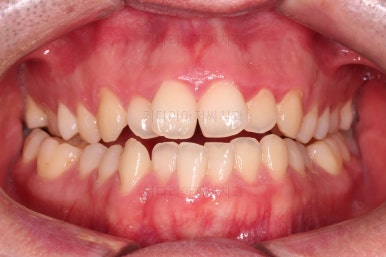

초진 시 입안의 모습입니다.

교합이 많이 안좋습니다.

위아랫니가 서로 엇갈려 가며 지그재그로 껴 들어가야 어금니 맞물림이 생기는데요.

이번 환자분은 아랫니, 아래턱이 전반적으로 앞으로 나와 있어서 교합이 전혀 안되고 있는 상태였습니다.

부산긴얼굴긴턱교정 전후 비교해 볼게요.

이렇게 비교해 놓으니 더 드라마틱하죠.

당연히 교합/위아래 폭 등 치열이 좋아졌고요.